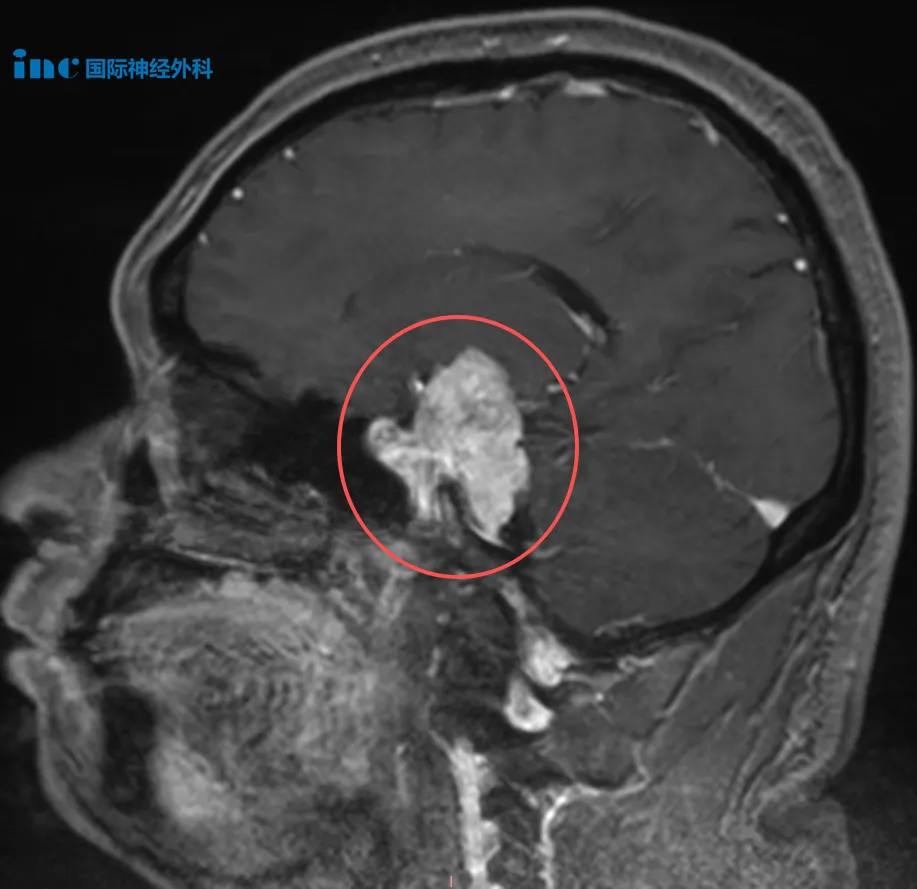

40岁男性左侧中、后颅窝占位性病变患者

吴先生意外发现左侧中、后颅窝团块状异常强化影,尺寸约38mm×28mm,疑似脑膜瘤,且已压迫脑干。患者表现为头昏不适、视物模糊、记忆力下降。延迟治疗是否存在巨大风险令其深感恐惧。咨询巴教授后,教授评估与患者担忧一致:“继续拖延无益,只会导致肿瘤进一步生长,增大手术难度,手术应尽早实施。”

巴教授指出吴先生的脑膜瘤较为罕见,具有不寻常生长延伸:向上延伸至左侧大脑内部,推压基底节、颞叶及下丘脑,同时影响视系统包括视神经和视交叉;向幕下延伸相当部分。肿瘤跨越颞叶区域及后颅窝两个不同颅内间隙,此种双向延伸需采用特殊手术技术。